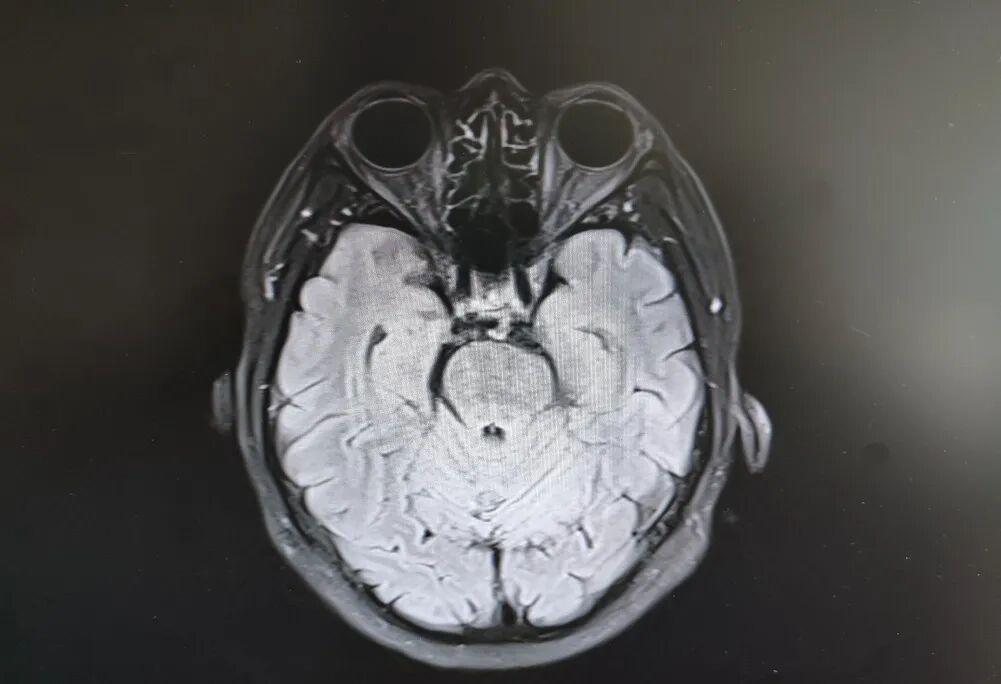

患者頭部磁共振影像